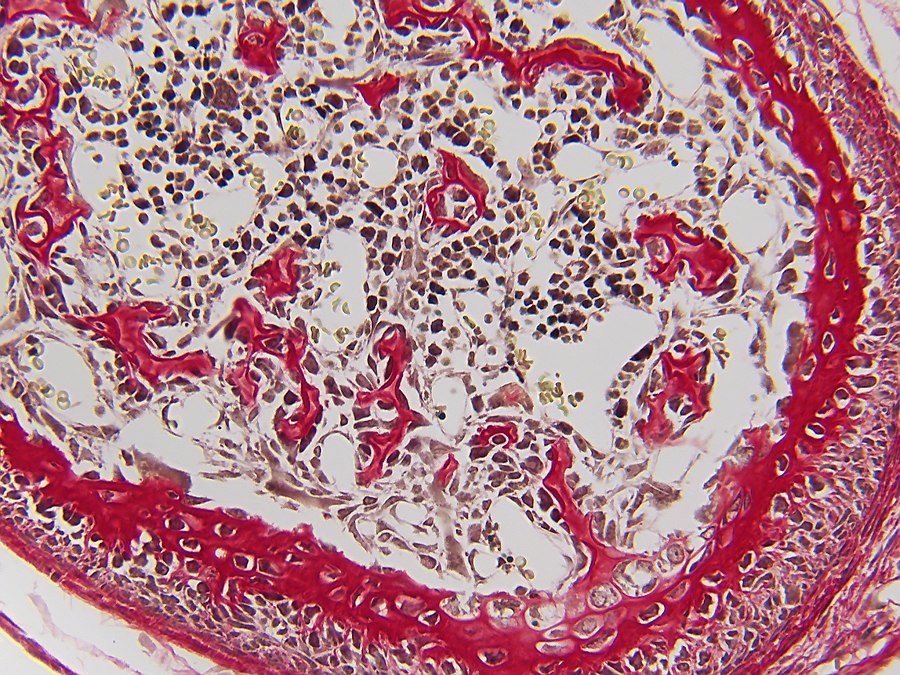

Bone formation or ossification[2] visualized by various histological stains.

In both cases, primary (braided or plexiform) bone is first formed, which is soon replaced by secondary (lamellar) bone, which may have a compact or spongy appearance macroscopically. During bone growth, areas of primary bone, bone breakdown, and secondary bone continually occur side by side. This coexistence of breakdown and creation (remodeling) continues in the adult body, although at a much slower rate.

Bone is composed of cells and intercellular material that is calcified, the bone or bone matrix. Three types of cells can be distinguished:

1. Osteoblasts (bone forming cells), which produce the organic components of the bone matrix. Osteoblasts arise from osteoprogenitor cells, which are found in endosteum[2] and periosteum[2]. Osteoblasts synthesize the organic components of the bone matrix and thus produce collagen type I, proteoglycans[2] and glycoproteins[2]. Osteoblasts are located in contiguous rows, the osteoblast hemisphere, against the surface of the bone;

2. Osteocytes (mature bone cells) formed by maturation of osteoblasts lie in cavities (lacunae) of the bone matrix. From these cavities, canaliculi run through the bone in different directions, containing the outgrowths of osteocytes. They make contact with each other through gap junctions[2], allowing the exchange of ions and small molecules;

3. Osteoclasts (bone-degrading cells); these are large multinucleated (up to fifty nuclei) cells that can break down bone. Osteoclasts are freely motile cells and lie as elongated cells against the bone margin, sometimes in a hollow created by them eating away matrix: the lacuna of Howship.

To observe the staining of bone forming tissue and the differences in staining, it was chosen to cut sections of similar tissue which was fixed in the same way. For this purpose, five-day-old mice were fixed in Bouin liquid. To allow the fixative to penetrate the tissue more easily, the extremities were removed and small incisions were made in the skin. Tissue was left in Bouin for approximately two months after which dehydration was started in ethanol 70%. The usual rinsing out of the fixative in water did not take place to prevent tissue from swelling too much[3]. Further ethanol steps were 85%, 95% and 100% with a duration of 48 hours per step. Via xylene, the switch to paraplast plus was then made. To ensure that all xylene was replaced with paraplast, three liquid paraplast baths were used.

- Trichrom according to Mallory from 1900[5];

- AZAN according to Heidenhain[6];